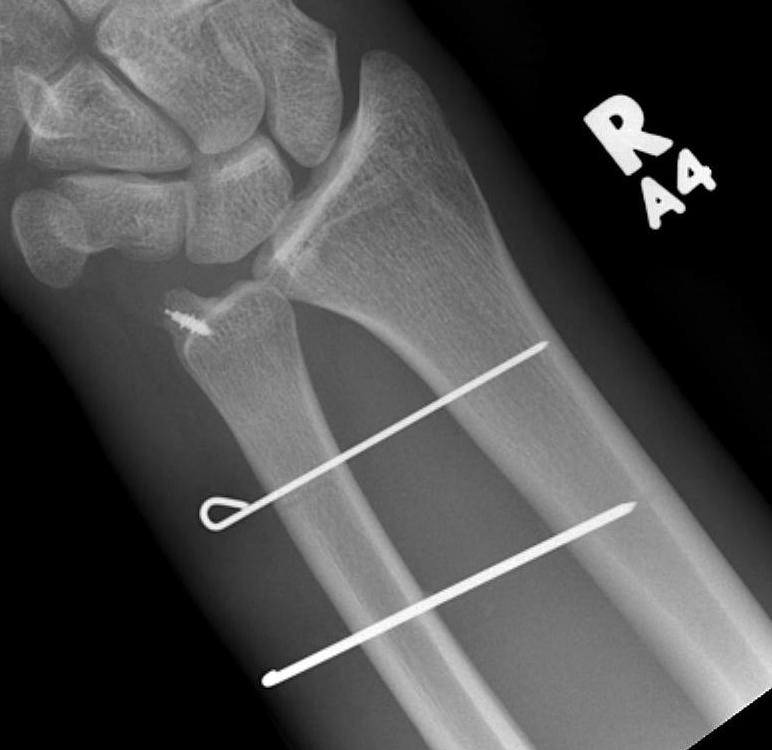

- ulna styloid ORIF

- +/- capsule repair

- +/- K wire fixation

Technique

AO surgery ulna styloid fracture screw fixation

AO surgery ulna styloid TBW fixation